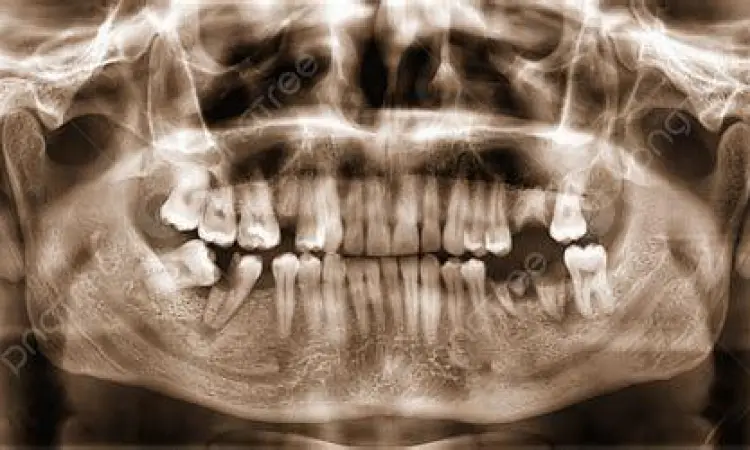

Seringkali, pasien hanya fokus pada harga awal pemasangan. Padahal, ada serangkaian biaya operasional selama masa perawatan yang wajib masuk dalam anggaran Anda. Pertama adalah biaya diagnostik awal, yang meliputi foto Rontgen Panoramik dan Sefalometrik untuk melihat struktur tulang rahang dan posisi akar gigi. Tanpa data ini, dokter tidak bisa membuat rencana perawatan yang akurat.